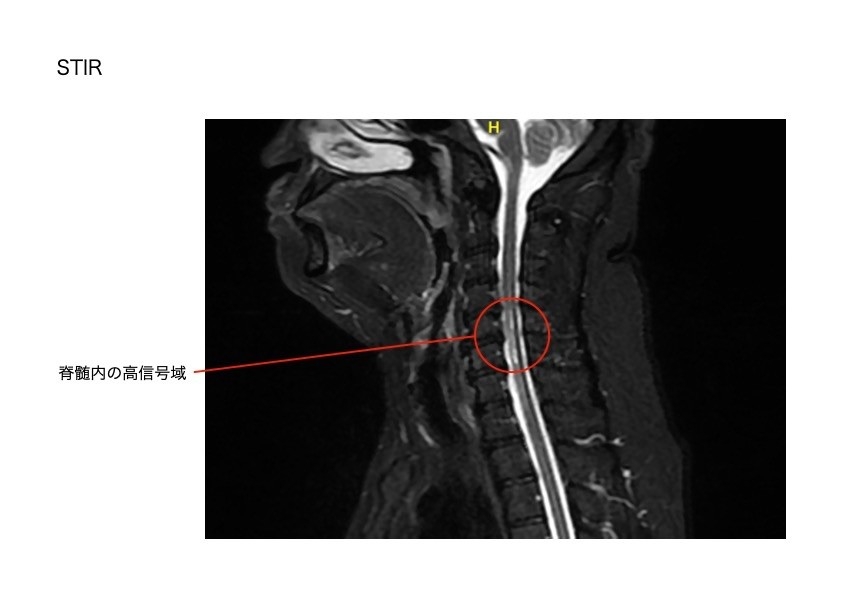

・脊髄梗塞 (前脊髄動脈症候群)

前脊髄動脈の支配領域である脊髄腹側約2/3錐体路と脊髄視床路に血流障害が生じます。

脊髄の中の動脈が血栓で詰まり、首から下の脊髄神経が壊死しました。